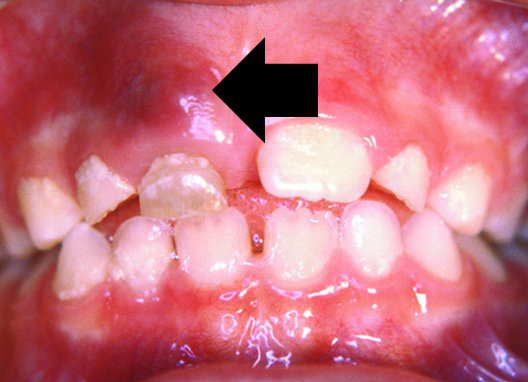

6.5 Eruption cysts

An eruption cyst occurs above an erupting tooth (deciduous and permanent teeth).

Signs and symptoms

An eruption cyst appears as a smooth, localised, dome shaped, fluid filled swelling. It is bluish in colour if it contains blood, is painless and overlies an erupting tooth.

Causes

The cyst is caused by abnormal follicular enlargement just before eruption. Trauma leads to bleeding within the follicle, producing the purplish brown appearance.

Age

Children aged between six months and 12 years.

Duration

The cyst drains once the tooth erupts; this length of time varies from individual to individual. However if it does not resolve within a couple of weeks refer to a dental professional as more serious but very rare conditions can present the same.

Treatment

Usually, no treatment is necessary unless the cyst becomes infected. In this case, a referral to a dental practitioner is required.